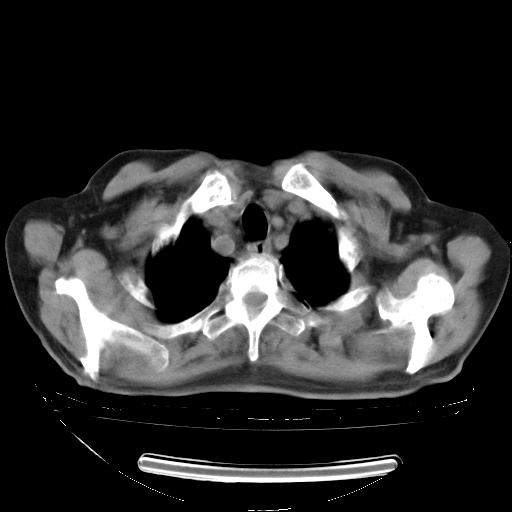

今天复查肺部CT,发现双肺广泛磨玻璃样改变。所以我把3月19日和5月9日相隔50天的肺部CT上传。请大家会诊。

2009年3月19日肺部CT片。

2009年3月19日肺部CT

5月9日肺部CT(在4月27日齐鲁医院肺部CT描述部分肺组织磨玻璃样改变,12天后肺组织广泛磨玻璃样改变)